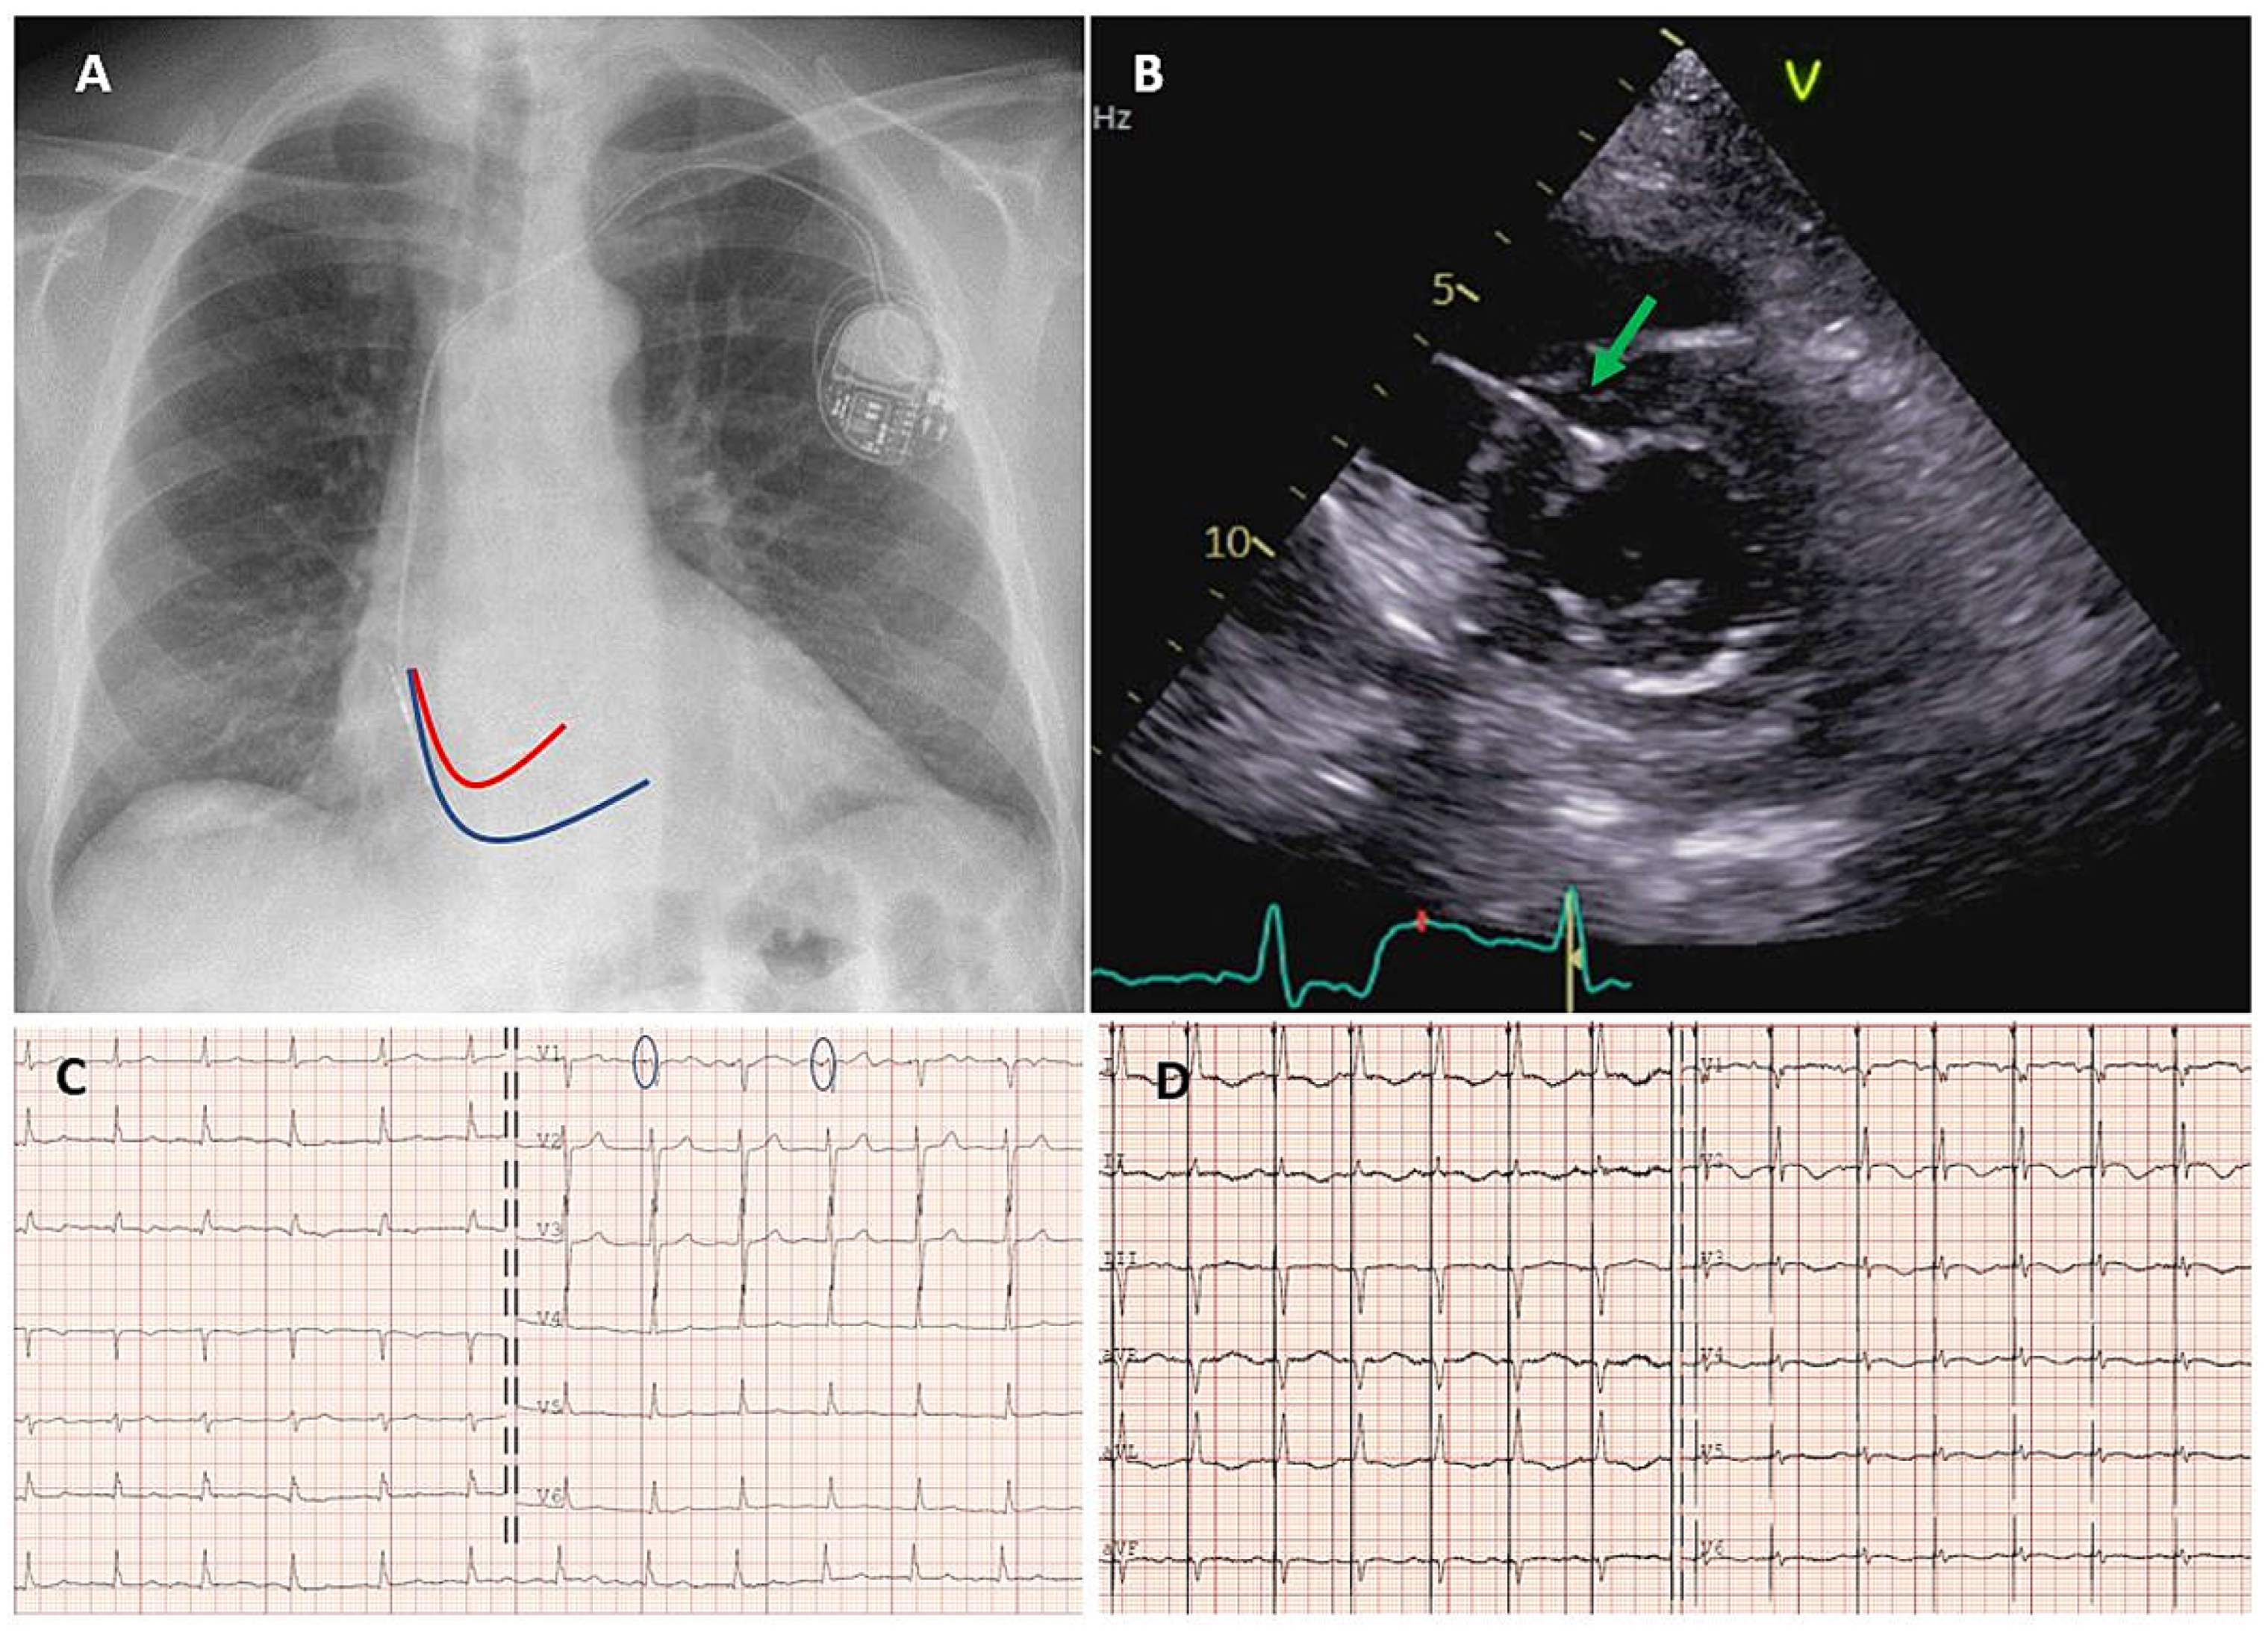

His bundle pacing

Implantation technique and success rates

Left bundle branch (area) pacing